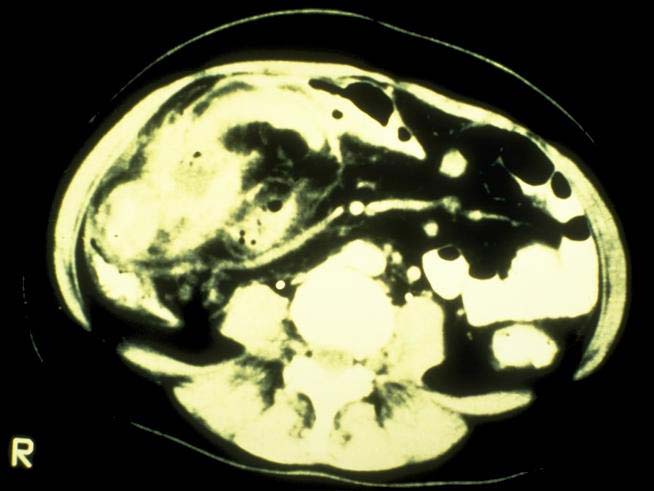

Abszesse (=Eiterhöhlen, meist im Zusammenhang mit einer Fistel),

das toxische Megacolon (=vor einer entzündlichen Verschwellung der Darmlichtung im S-Darm oder an der haarnadelförmigen linken Flexur (Dickdarm-Kurve) kommt es zu einer Stauung des Darminhaltes mit massiver Aufweitung der Darmschlinge: in schweren Fällen platzt (perforiert) der Darm und es bildet sich eine gefährliche Bauchhöhlenentzündung);(A17,A79,A19)

Stenosen (=Verengungen) oft an der Bauhin´schen Klappe (Übergang zwischen Dünndarm und Dickdarm, narbig oder entzündlich, mit der Gefahr eines Subileus (=inkomplette Darmlähmung);